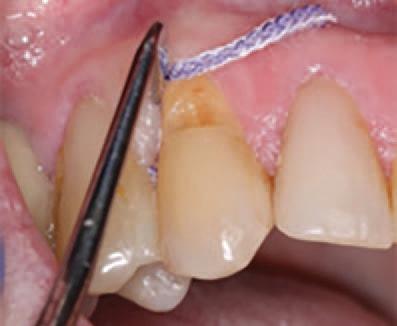

To improve isolation and soft tissue access, a retraction cord was placed before initiating the procedure (Fig. 2). The tooth was evaluated using a caries indicator dye (Kuraray Noritake Dental), helping to identify any remaining infected tissue beneath the dislodged composite (Fig. 3). Decay removal was completed with a diamond bur, and the enamel was bevelled using a starburst pattern to enhance aesthetic blending (Fig. 4). This preparation design was chosen for visual integration rather than bond strength enhancement.

Application of caries indicator dye to identify remaining infected tissue beneath the dislodged composite.